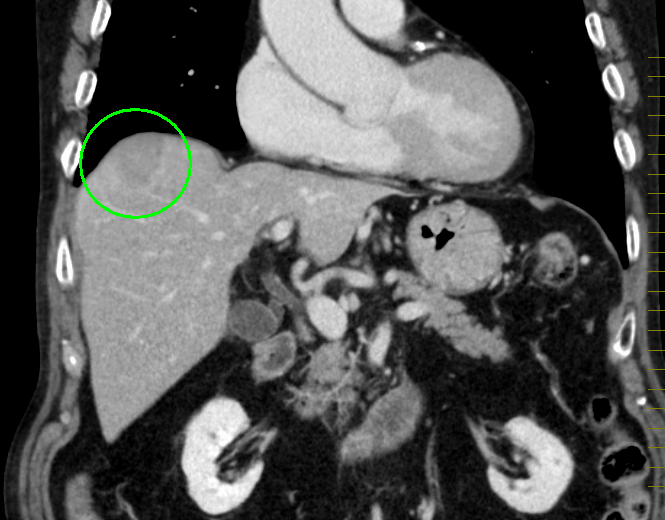

肝臓がんの検査としては、まず血液検査(肝機能検査、腫瘍マーカー検査)と超音波(エコー)検査を行います。必要により、CT検査もしくはMRI検査による画像検査も組み合わせて実施します。画像検査で良性/悪性の鑑別が難しい場合は、直接腫瘍組織を採取して調べる検査(針生検)を追加する場合もあります。

MRI画像